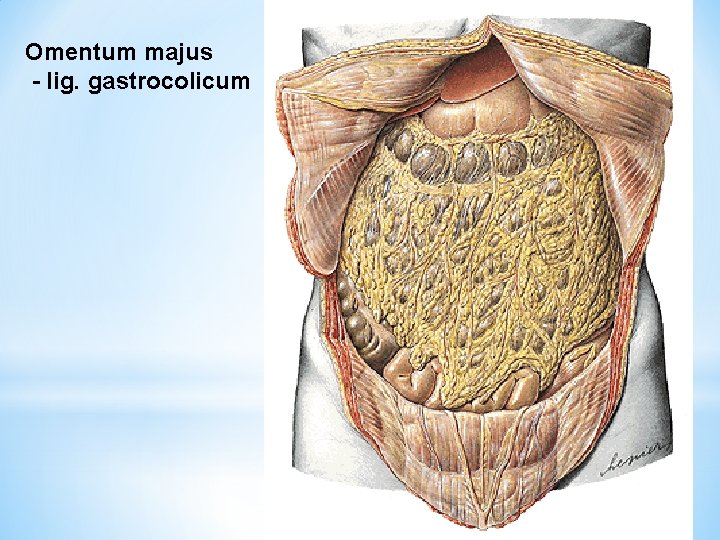

Omentum majus - lig. gastrocolicum